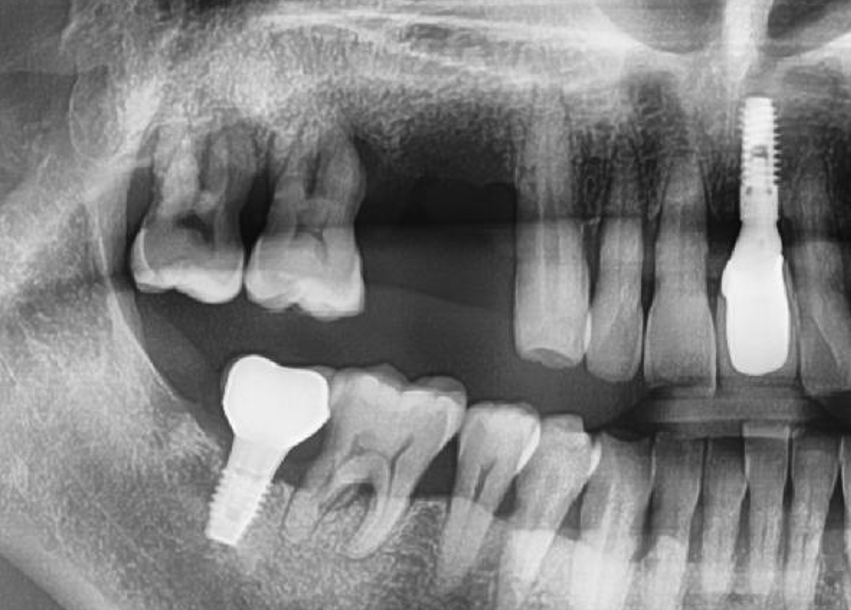

56세 남환으로 수년전 #14의 발치를 했고 #15는 1개월 전 발거가 되었으며 #16, 17은 만성복합치주염으로 심한 동요를 보이고 있었다. 치료계획은 #14, 15, 16 부위에 3개의 임플란트를 식립하기로 했다. 술전 파노라마사진에서 #14, 15의 결손과 #16, 17의 심한 치조골 소실을 관찰할 수 있다 [그림 2].